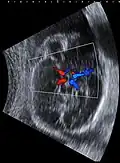

Fetal ultrasound image at the level of circle of Willis, showing PCA, MCA and ACA